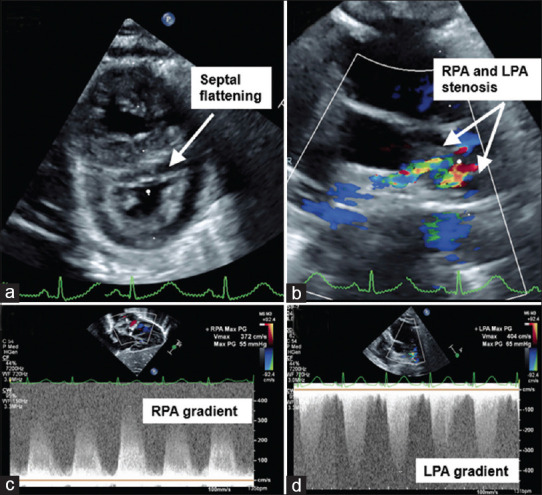

Pseudoaneurysm formation within the right ventricular outflow tract (RVOT) is a rare but serious complication following cardiac surgeries involving the RVOT. This report presents the case of a 3-month-old, 4 kg infant with tetralogy of Fallot and pulmonary atresia, previously treated with ventricular septal defect closure and right ventricle (RV)-pulmonary artery homograft placement. The patient presented critically ill with septic shock and suprasystemic RV pressure. A high-risk surgical approach was averted through the endovascular exclusion of the pseudoaneurysm using a Gore VBX® balloon expandable covered stent, in addition to stenting of bilateral proximal branch pulmonary arteries to alleviate RV hypertension. This case underscores the multifactorial nature of RVOT pseudoaneurysm formation and the importance of a high index of suspicion for diagnosis. Management options, including surgical and transcatheter strategies, are discussed, focusing on the successful use of a covered stent for stabilization in a critically ill patient.